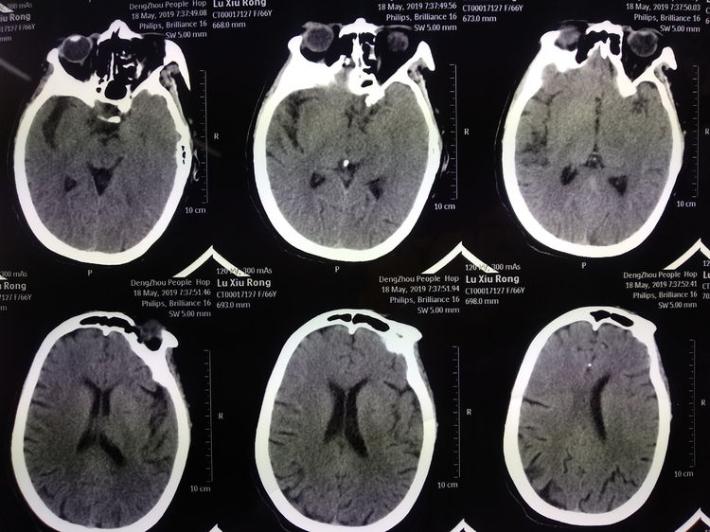

术后即刻复查头部CT

患者术后1天,左侧肢体肌力0级,NIHSS评分:12分,复查头部CT:右侧基底节区出血,范围约22mmX49mm,请脑外科会诊:做好立体定向穿刺准备,注意观察患者病情变化,密集复查头部CT。

术后3天复查头部CT

术后7天复查头部CT

术后15天复查头部CT

术后21天复查头部CT

术后复查头部CT:左侧丘脑血肿无扩大,未见造影剂渗漏。